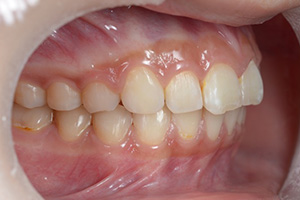

矯正治療のCASE 02

Before

After

- 主訴

- 上顎前歯が出ていて口が閉じにくい

- 治療内容

- 上顎前突・出っ歯の非抜歯による歯並び治療

- 治療費用

- 88万円~(税込)

- 治療期間

- 12ヶ月

【リスク・副作用】

歯の痛み、口内炎、歯磨きがしにくいことによるむし歯や歯周病のリスク、歯根吸収や歯の変色、後戻りなどの副作用があります。